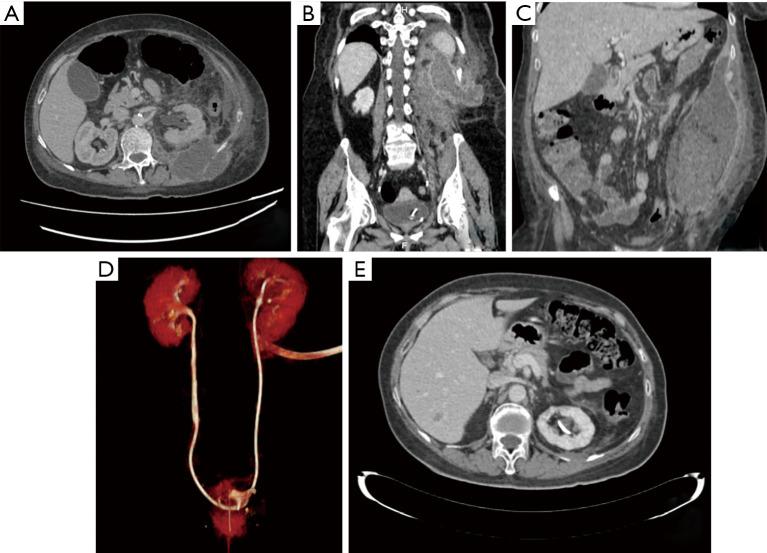

Spontaneous urinoma is a urological entity that can be complicated by a retroperitoneal abscess. Urinoma can be iatrogenic, traumatic, or can be caused by obstructive uropathy. We report two cases of spontaneous urinomas, describing a not previously published cause of urinoma: pyeloureteritis. (I) A 55-year-old Caucasian female started with intense left-sided flank pain for 3 days. CT scan revealed a voluminous retroperitoneal abscess, which extended through the posterior pararenal space and the left lumbar paravertebral musculature. (II) A 48-year-old Caucasian male presented with constitutional symptoms over the previous 2 months and investigations showed a voluminous urinoma and marked pyeloureteritis findings on CT scan. Both patients were managed by endoscopic placement of a double-J stent and drainage of the collection (open and percutaneous approach, respectively). Urinoma was confirmed by fluid biochemical analysis, which demonstrated that fluid creatinine was markedly raised as compared to the serum creatinine. Urinoma in the absence of obstruction or trauma is rare. These two case reports highlight one of the conditions leading to urinoma and the management of retroperitoneal abscess. Pyeloureteritis is a cause of spontaneous urinoma and it should be considered in the lack of another obstructive cause.

自发性尿囊肿是一种泌尿系统疾病,可并发腹膜后脓肿。尿囊肿可能是医源性、外伤性的,也可能由梗阻性尿路病引起。我们报告两例自发性尿囊肿病例,描述一种此前未报道过的尿囊肿病因:肾盂输尿管炎。(I)一名55岁的白种女性开始出现左侧剧烈腰痛3天。CT扫描显示一个巨大的腹膜后脓肿,延伸至肾后间隙和左侧腰大肌。(II)一名48岁的白种男性在过去2个月出现全身症状,检查显示CT扫描有一个巨大的尿囊肿和明显的肾盂输尿管炎表现。两名患者均通过内镜置入双J支架及引流积液(分别采用开放和经皮穿刺方法)进行治疗。通过液体生化分析证实为尿囊肿,结果显示与血清肌酐相比,液体肌酐显著升高。无梗阻或外伤情况下的尿囊肿很罕见。这两例病例报告强调了导致尿囊肿的一种情况及腹膜后脓肿的处理。肾盂输尿管炎是自发性尿囊肿的一个病因,在没有其他梗阻性病因时应考虑到这一点。